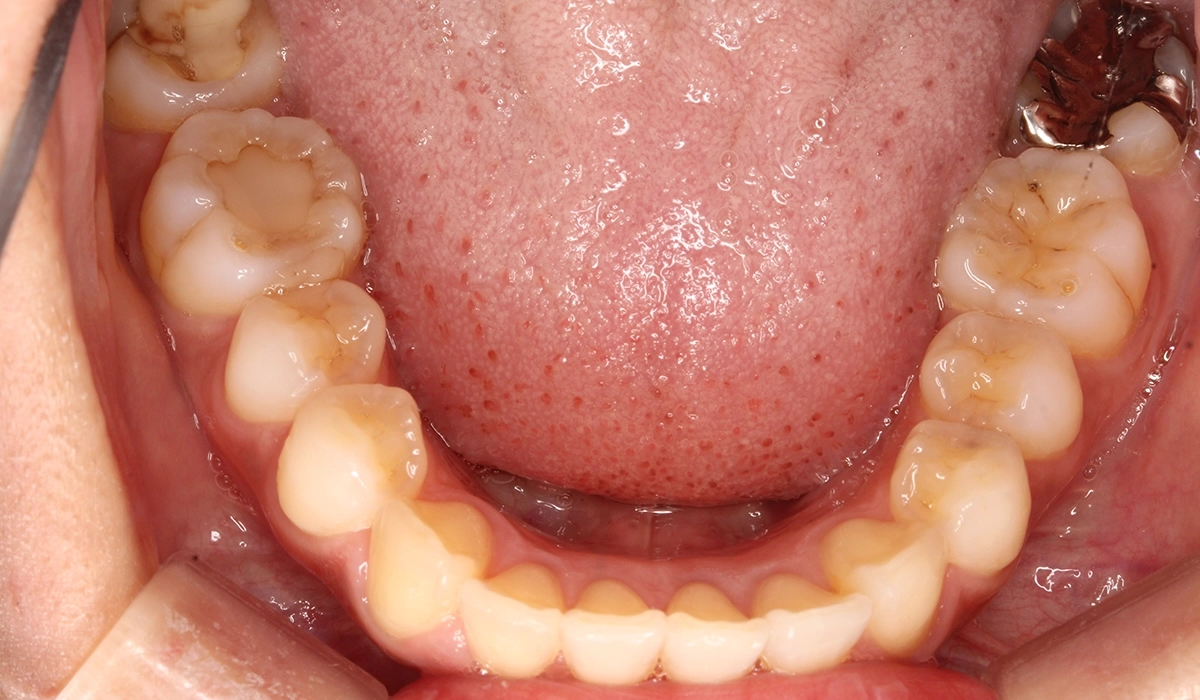

術前:下顎

術後:下顎